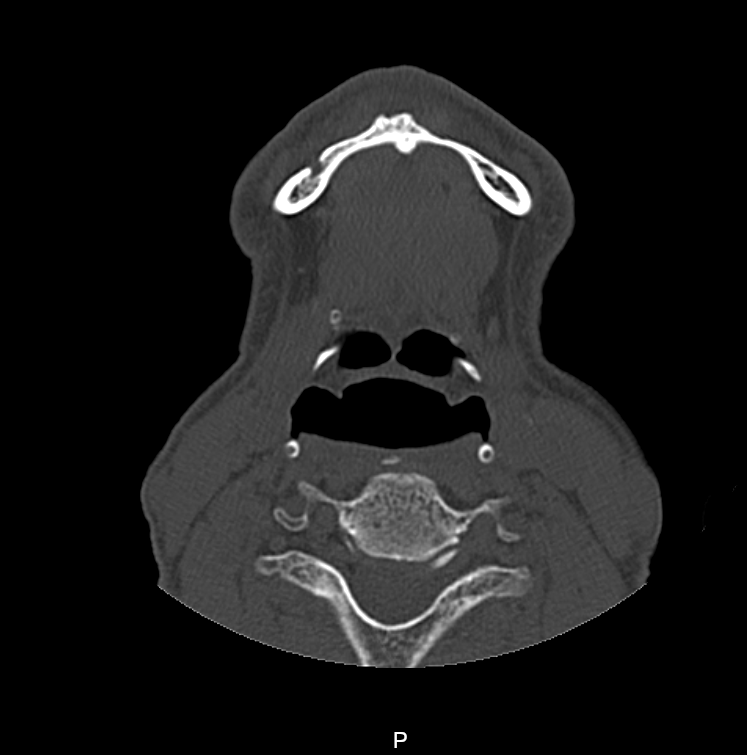

A Tomografia Computadorizada de Mandíbula é um exame de diagnóstico por imagem da mandíbula, a qual é formada por cinco partes e responsável pelo movimento de mastigação.